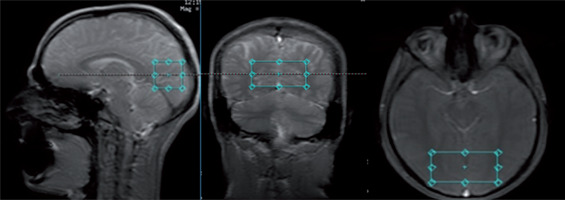

In this cross-sectional study, MR studies were performed with a 3T GE Discovery 750w scanner with a 70 cm wide bore, using a body transmit coil for excitation and the eight-channel receiver coil (description available in the GE catalogue). Each MR session consisted of structural imaging performed for voxel placement and localized single-voxel proton MR spectroscopy. The structural scan was obtained using steady-state fast spin echo (SSFSE) with 3 slices in each orthogonal plane, with the following parameters: repetition time/echo time (TR/TE) = 6.412/2.1 ms, duration 30 s. Spectroscopic data were acquired with a PRESS PROBE-P single voxel sequence (TR/ TE = 1500/35 ms and TR/TE = 1500/288 ms, bandwidth = 2367 Hz, 128 acquisitions, duration 3 min 48 s), with chemical shift selective (CHESS) water suppression. The spectra were acquired with a short echo time (35 ms) to measure Glu and Glx and with a long echo time (288 ms) to measure Lac. Both spectra were acquired within the same volume of interest (VOI, 30 × 30 × 60 mm = 54 cm3), which was placed in the vicinity of the occipitoparietal grey matter area (Fig. 1). A large VOI was used to allow for monitoring of small signals from Glu and Glx within reasonable time.

FIG. 1

Placement of the volume of interest (30 × 30 × 60 mm3) in the area encompassing the occipito-parietal cortex of both hemispheres.